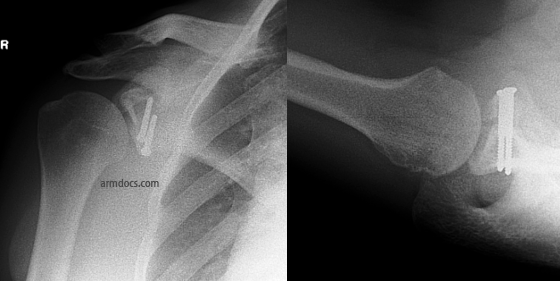

The procedure is performed under a combination of general and regional anaesthesia. The skin on the front of the joint is incised and the subscapularis tendon is split. The inside of the joint is examined. The rim of the socket is freshened to promote bleeding and facilitate healing. A bone block is prepared using the coracoid process (a part of the shoulder blade) or bone taken from the pelvis and repaired to the defect in the socket using 2 screws and occasionally a mini-plate (these procedures are referred to as the Latarjet or Eden-Hybinette procedures respectively). In selected patients the bone block may be positioned and fixed arthroscopically using a pair of suture-button devices. The labrum and capsule is fixed back to the rim of the socket with suture anchors (small devices with sutures that are embedded in bone).

An appointment will be arranged for you at 2-4 weeks after the procedure. Follow-up is required for at least 12 months after surgery or until a satisfactory recovery is achieved. This will include X-rays at interval to check bone healing.